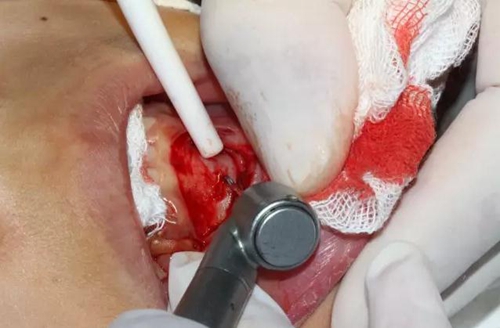

口腔局部浸潤麻醉,手術(shù)鋪巾

切開、翻瓣

去除骨皮質(zhì),暴露牙冠大部分